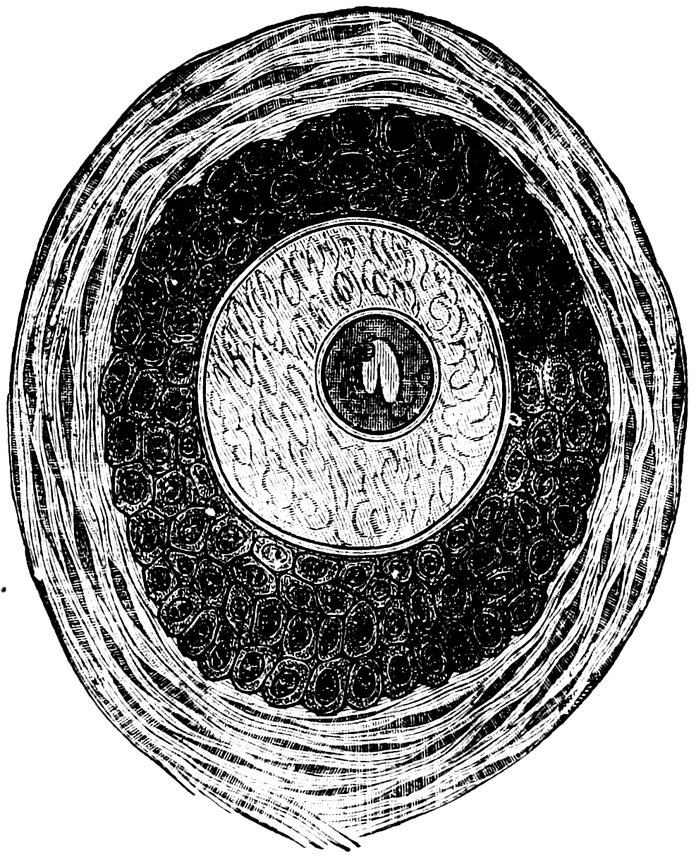

| 16. | Ripening follicles | 61 |

| 17. | Graafian follicles | 62 |

| 86. | Diagrammatic Representation of the Graafian Follicle | 585 |

We must first consider the changes in the ovaries, which play an etiologically important part. At the onset of puberty, the follicular masses of the ovary exhibit a more active growth, the follicles increase in size, with their contained ova they approach the surface, and finally, by the bursting of the follicles, the ova are extruded. Then, in the life-phase in which conception occurs, and under the influence of the hyperæmia of all the pelvic viscera that accompanies this process, a notable development of the corpus luteum takes place, this latter body reaching its maximum size in the eleventh week of pregnancy, subsequently undergoing involution and leading to the formation of a considerable scar. Finally, in the critical period of life in which the menstrual flow ceases, a continually increasing growth and new formation of connective tissue-stroma takes place in the ovaries at the expense of their cellular constituents, and a regressive metamorphosis of the graafian follicles occurs.